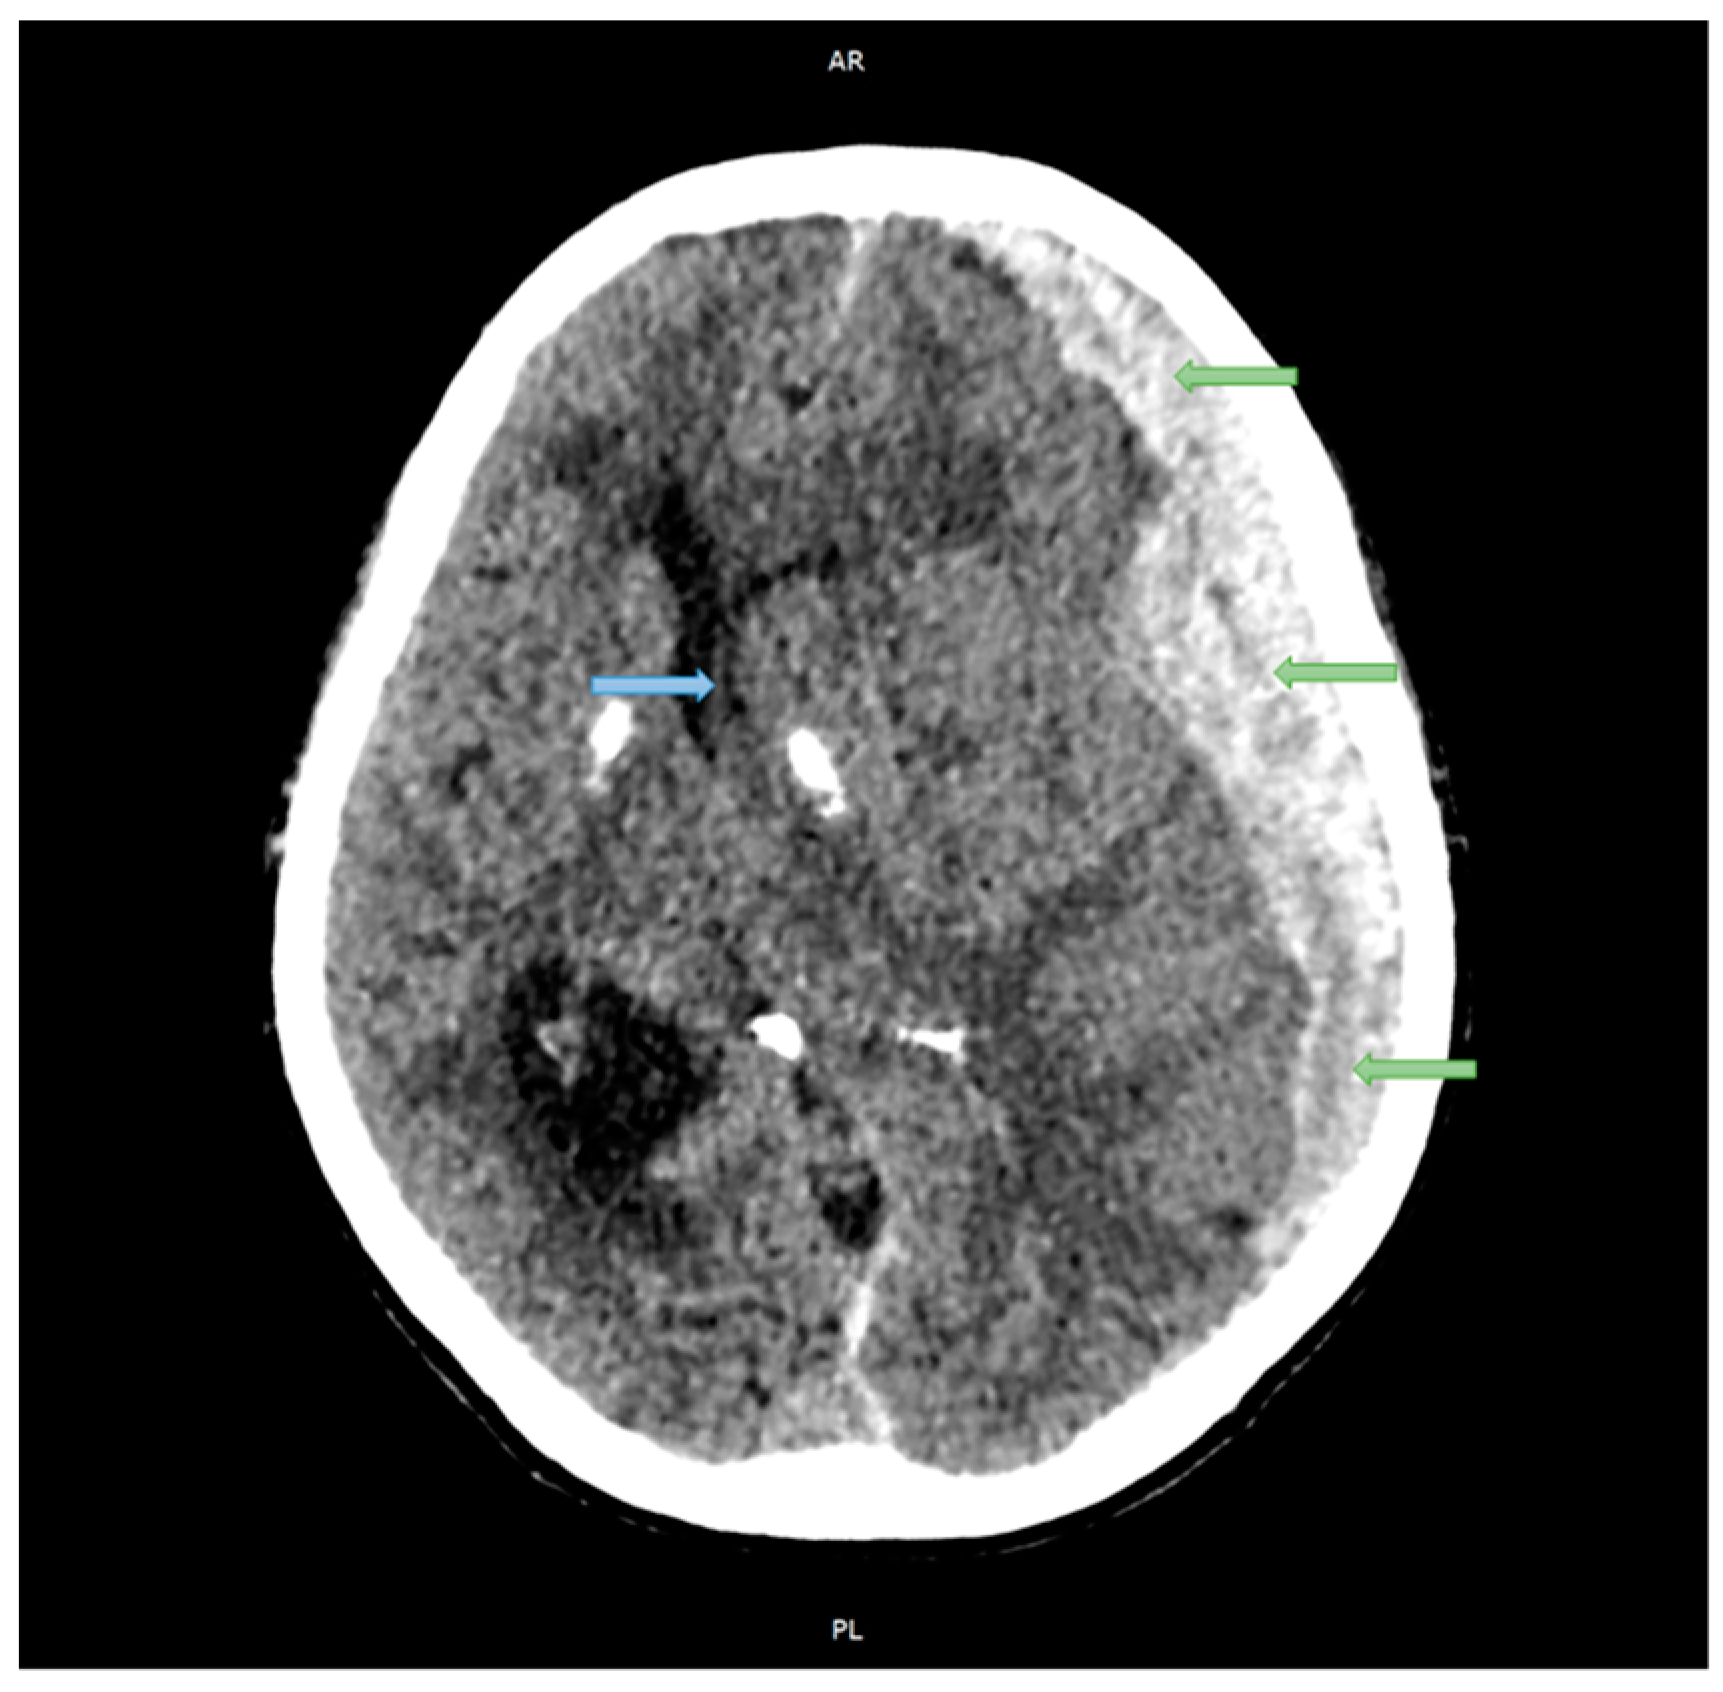

2.1. Case Studies